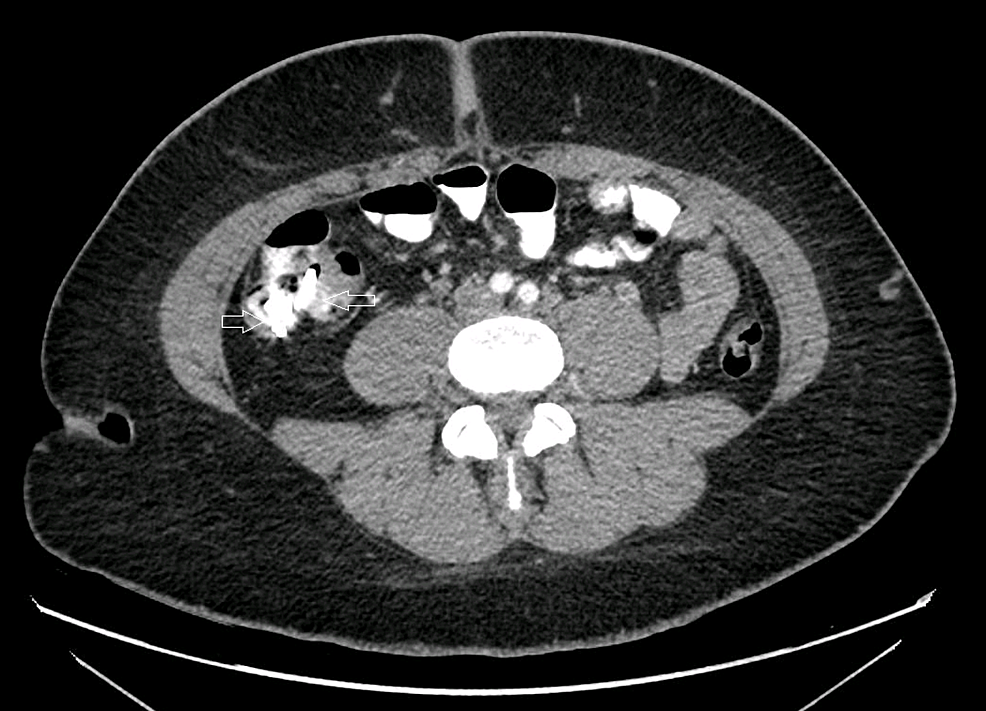

Pepto Bismol X Ray Examination that produces images of the. The ed was going to. Examination that produces images of the.